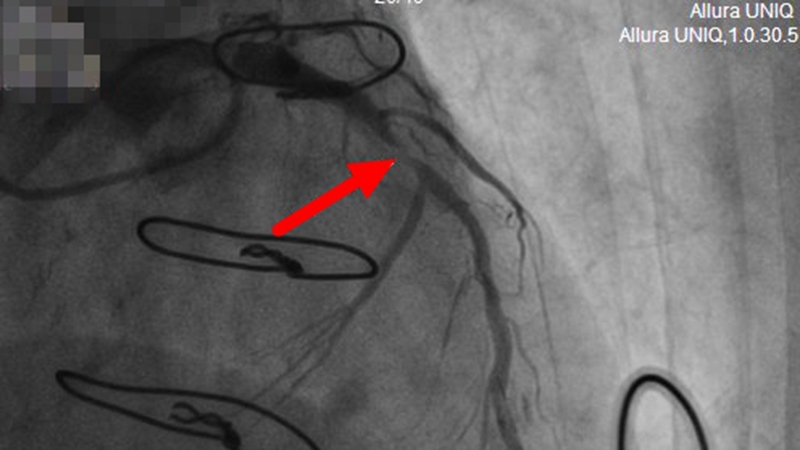

【术前,前降支近段严重狭窄】

桥梁堵塞无法再通,那就另寻他路。救心团队当机立断,果断决定翻修老路,在5年前就闭塞掉的前降支近段植入支架。